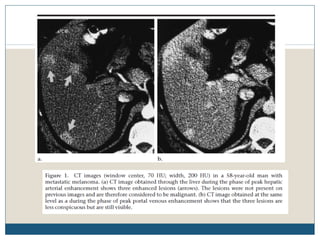

Fígado

 O fígado é um local comum de doença metastática, com séries de autópsia

sugerindo a presença de envolvimento hepático em até 58% dos pacientes

com melanoma metastático.

 Metástases hepáticas podem aparecer parcialmente calcificadas ou

hemorrágicas, e se for grande, pode conter áreas de necrose. O padrão de

reforço após a injecção de contraste pode ser uniforme, heterogêneo, ou em

forma de anel.

 Enquanto TC é o procedimento inicial de escolha para a imagiologia

anatómica do fígado, a ressonância magnética pode ser útil na identificação

de lesões solitárias tais como hemangiomas ou outras entidades benignas.

 Em imagens de RM, lesões metastáticas aparecem como áreas de hipossinal

em T1 e sinal moderadamente elevado em T2, enquanto hemangiomas são

caracteristicamente bem circunscritos.

 No ultra-som, metástases de melanoma são tipicamente hipoecóicas, e

hemorragia deve ser suspeitada se as lesões aparecerem heterogêneas.

 A metástase hepática subcapsular de melanoma pode ser uma causa rara

de um hematoma subcapsular ou hemorragia peritoneal.

Fígado  O fígadoé um local comum de doença metastática, com séries de autópsia sugerindo a presença de envolvimento hepático em até 58% dos pacientes com melanoma metastático.  Metástases hepáticas podem aparecer parcialmente calcificadas ou hemorrágicas, e se for grande, pode conter áreas de necrose. O padrão de reforço após a injecção de contraste pode ser uniforme, heterogêneo, ou em forma de anel.  Enquanto TC é o procedimento inicial de escolha para a imagiologia anatómica do fígado, a ressonância magnética pode ser útil na identificação de lesões solitárias tais como hemangiomas ou outras entidades benignas.  Em imagens de RM, lesões metastáticas aparecem como áreas de hipossinal em T1 e sinal moderadamente elevado em T2, enquanto hemangiomas são caracteristicamente bem circunscritos.  No ultra-som, metástases de melanoma são tipicamente hipoecóicas, e hemorragia deve ser suspeitada se as lesões aparecerem heterogêneas.  A metástase hepática subcapsular de melanoma pode ser uma causa rara de um hematoma subcapsular ou hemorragia peritoneal.